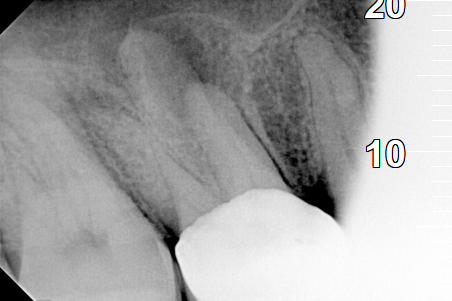

Final photo of the tooth after the root canal treatment

AFTER